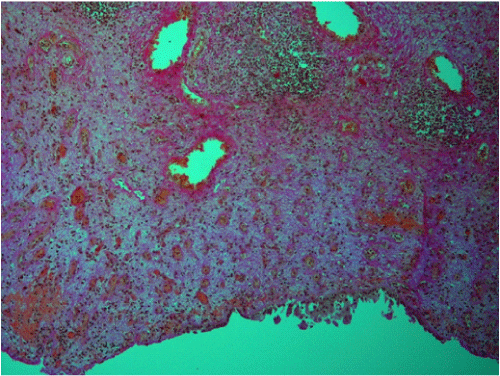

| Figure 6: Chronic erosive cystitis. Wide erosion of bladder epithelium (bottom). Lamina propria shows neoangiogenesis (granulation tissue), edema and early collagenic fibrosis. Focal mononuclear inflammatory infiltration, formation of lymphoid follicles, and more mature fibrosis (top). van Gieson, x120. |